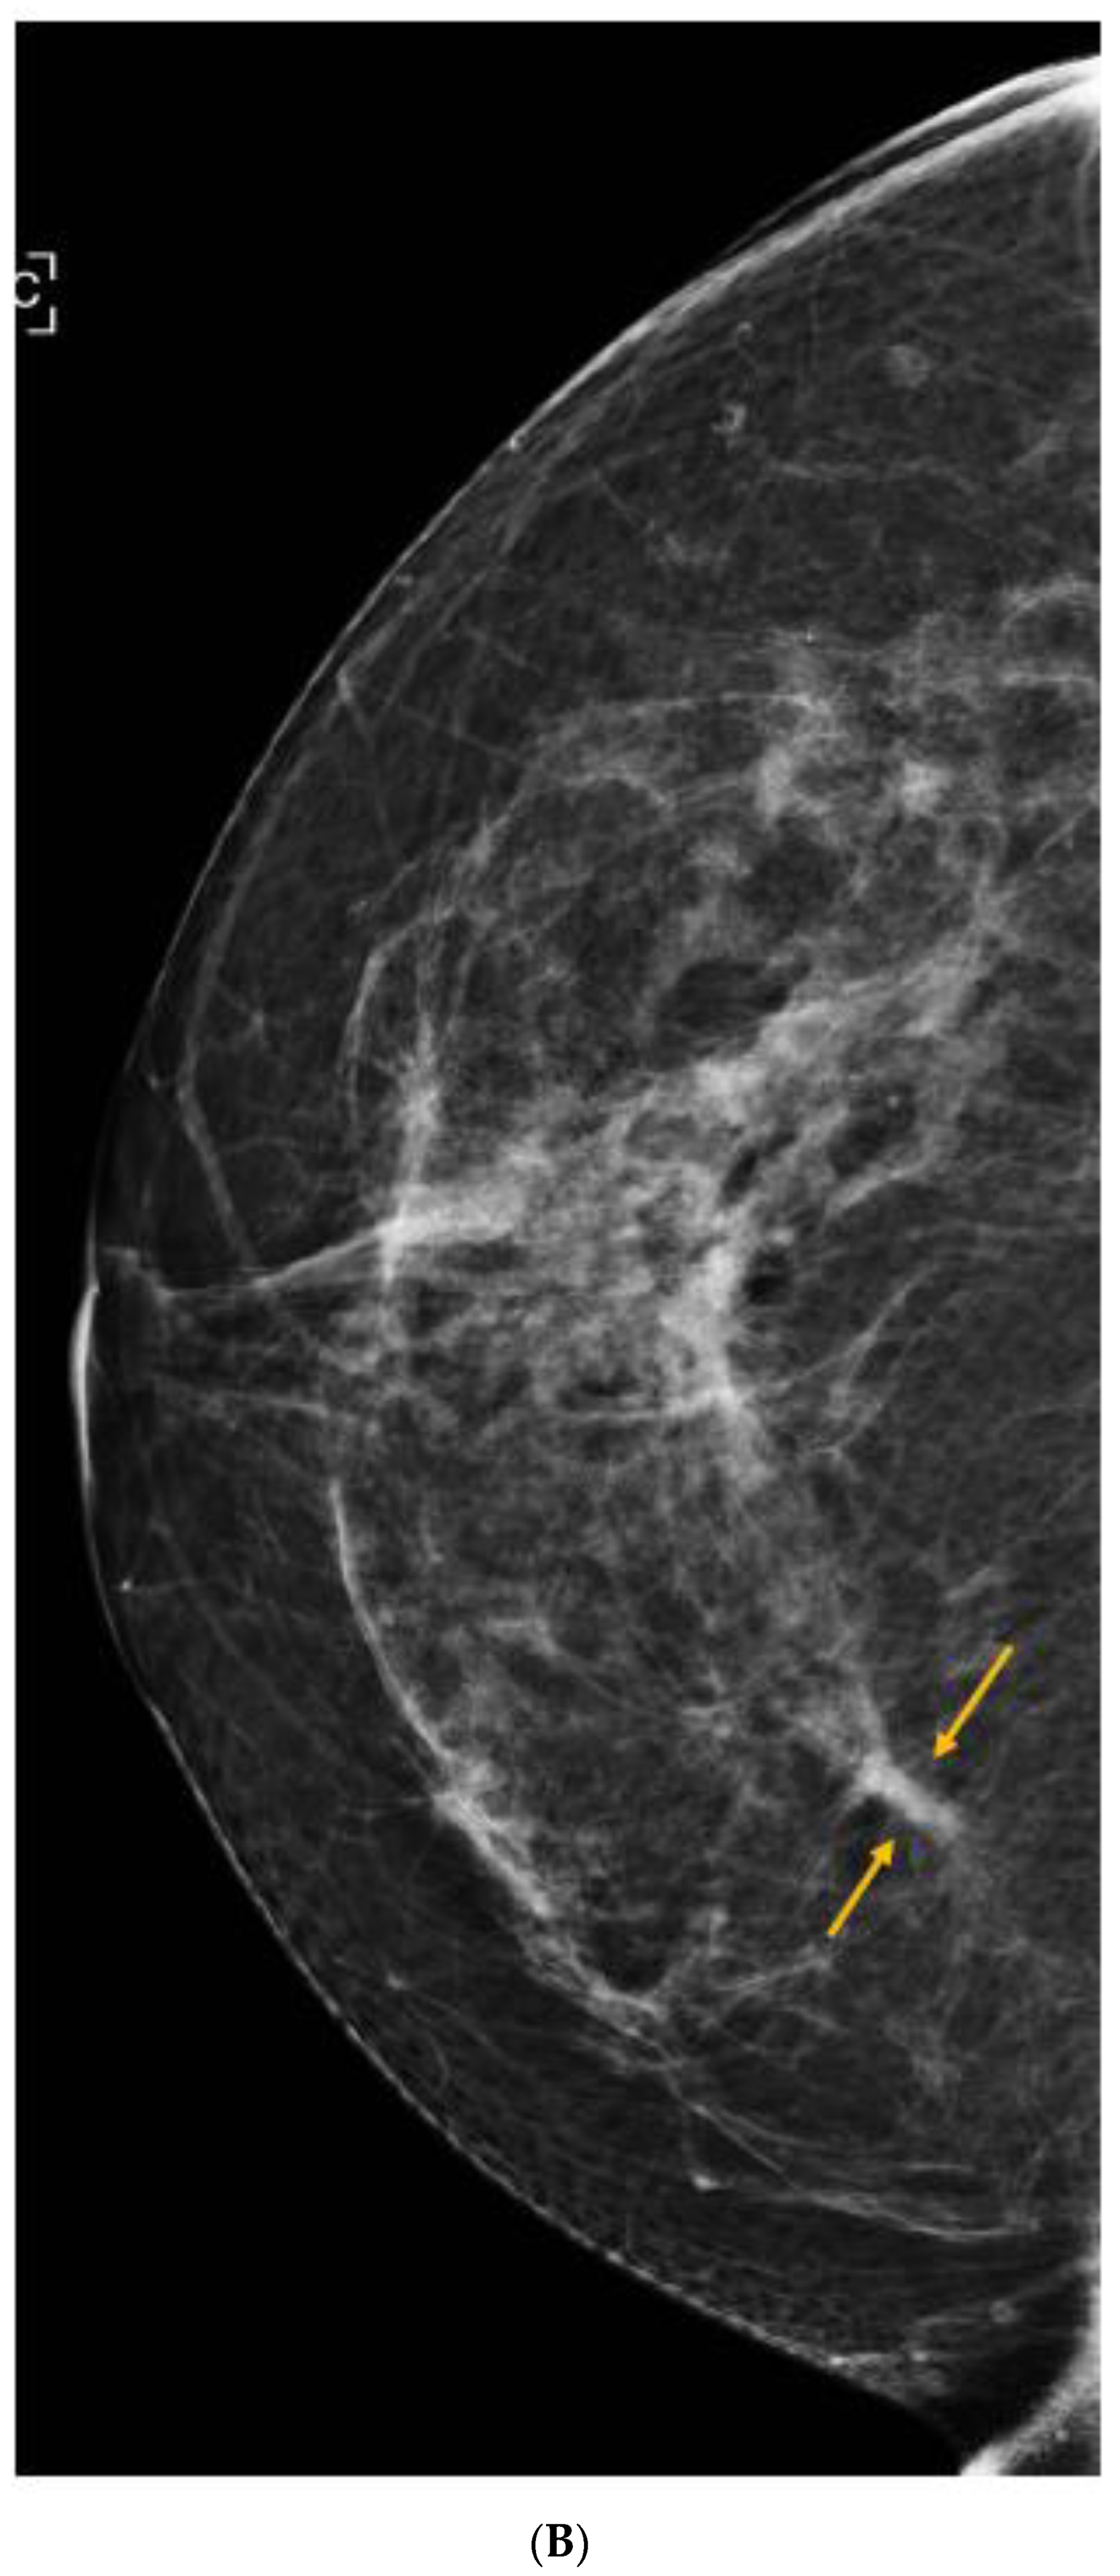

6. Digital Breast Tomosynthesis (DBT)